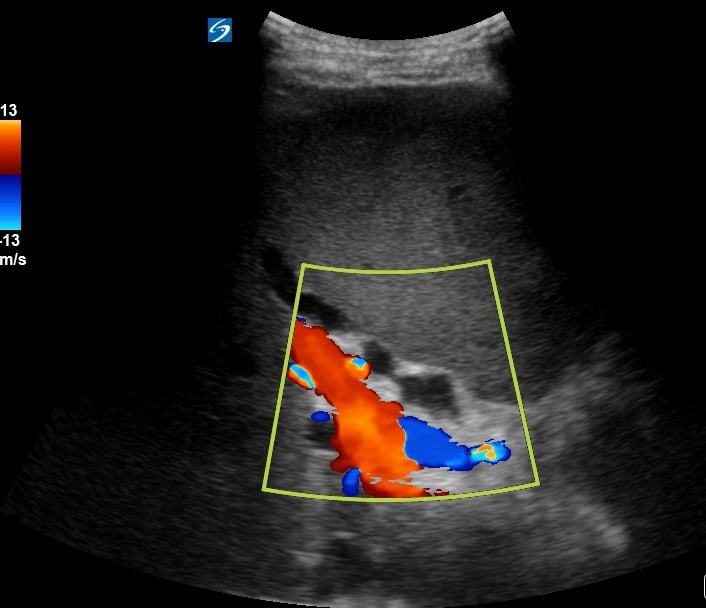

In abdominal ultrasound, biliary sludge refers to a viscous mixture of particulate matter, primarily cholesterol crystals and calcium bilirubinate granules, suspended in bile. Often appearing as a mobile, non-shadowing layer within the gallbladder, it indicates impaired gallbladder motility or bile stasis. While sometimes asymptomatic, sludge can lead to biliary colic, cholecystitis, or pancreatitis, making its detection crucial in medical diagnostics.

Ultrasound is the primary modality for identifying abdominal sludge due to its non-invasive nature and real-time visualization capabilities. Its presence highlights the need for clinical correlation and, in symptomatic cases, may necessitate lifestyle modifications or medical intervention to prevent further complications. Understanding biliary sludge on ultrasound is key for accurate abdominal assessment and patient management.